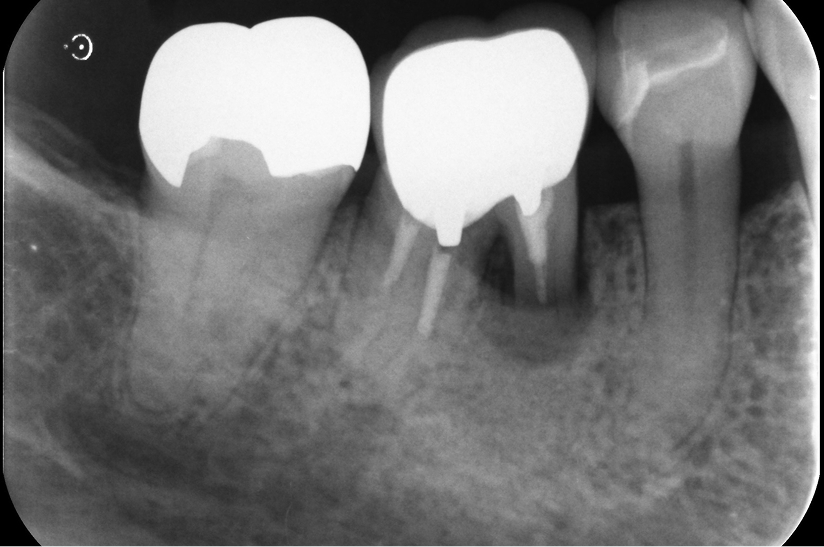

骨造成により

理想的な骨幅を回復させた

インプラント症例

タップで写真の拡大ができます。

Before

After

Under Treatment(俯瞰)

After(側方)

主訴

右下奥歯で噛むと痛みがある

診断

歯周病による歯槽骨吸収および垂直性歯根破折

治療方針

遊離端欠損となるため、入れ歯またはインプラントが選択肢となる症例。 硬いものをしっかり噛みたいという希望があり、インプラントを選択した。

また、水平的な骨吸収が認められたため、 インプラント埋入と同時にGBRを併用する方針とした。

治療内容

抜歯即時インプラント埋入およびGBR

治療期間

約6〜8ヶ月(骨造成を伴うため)

治療費用

1,500,000

結果

水平的に十分な骨幅が獲得され、インプラントの安定も良好に得られている。

治療の

リスク

創部の早期裂開が生じた場合、移植材の除去および再手術が必要となる可能性、下顎神経麻痺、出血・血腫

考察

骨量が不足する症例においては、GBRを先行して行う方法も選択肢となる。

本症例では抜歯窩からの血液供給も利用し、インプラント埋入と同時にGBRを行うことで、良好な骨造成と治癒が得られた。

その結果、治療期間の短縮と外科的侵襲の低減が可能となった。